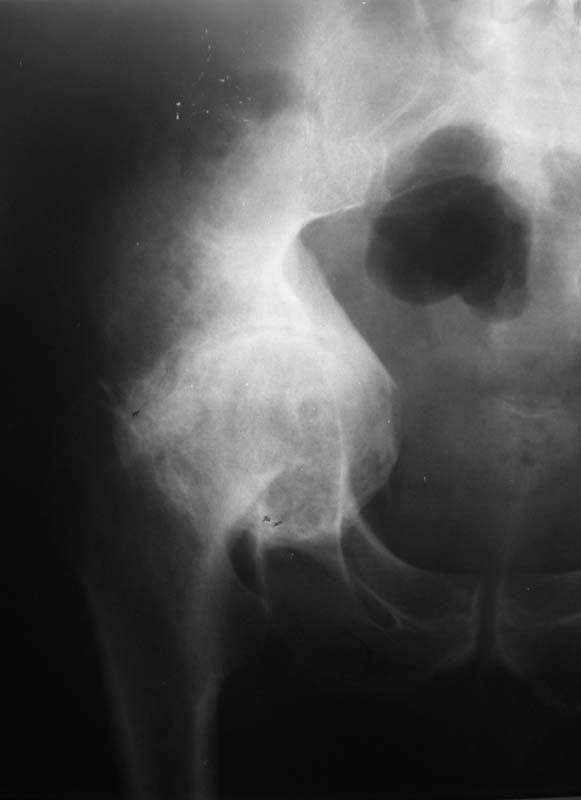

Мужчина, 54 г. В 12 лет перенес травму правого тазоберенного сустава.

Клинически движений в суставе нет, хотя при ходьбе беспокоят боли.

Предполагаем имплантацию <чашки> протеза в сформированное ложе без удаления головки бедра.

Ваше решение абсолютно адекватное и возражений нет, но проблема будет не в этом. У Вас будут сложности в 1) правильной ориентации чашки относительно истинной вертлужной впадины и 2) создании необходимого

"оффсета", попросту говоря, будет крайне сложно "оторвать" бедро от таза. Для этого мы в своей практике пользуемся расширенным передним и задним релизом, как правило, на это уходит достаточно много времени.